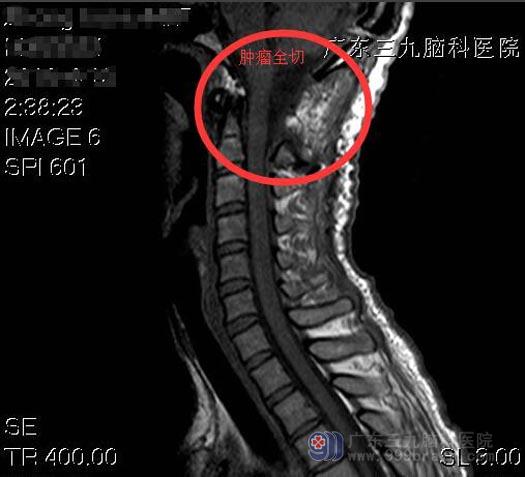

综合神经外科鲁明主任告诉他,肢体麻木症状就是这个病灶所引起,一经确诊,建议手术切除。王老师了解病情后,同意手术方案。鲁明主任主刀,在全麻下行枕骨大孔区偏左侧-颈2水平椎管内脊膜瘤切除术,术中见枕骨大孔区偏左侧-颈2水平椎管内灰柏色肿瘤组织,质软,包膜完整,分块予以全切除,术中对神经保护良好。术后,王老师的四肢麻木感明显好转。病理回报:血管瘤型脑膜瘤,WHO I级。